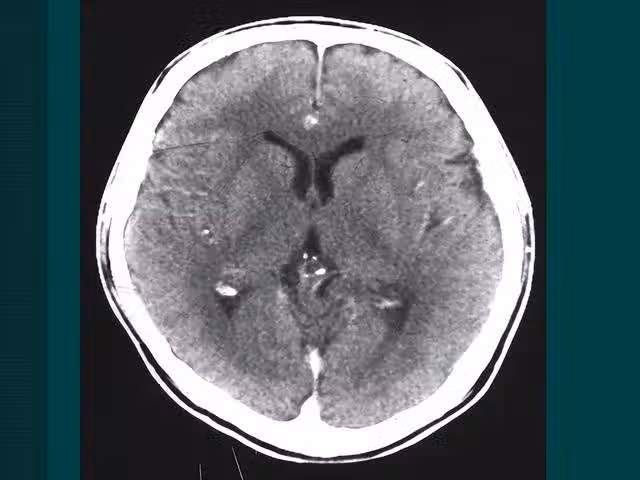

55歲男子夜間突發腦溢血!提醒:腦溢血來臨前,常有3個「預警」

第②個:頭暈頭痛

很多人會把頭暈頭疼不當回事,但如果經常出現頭暈頭痛的症狀,就一定要小心,最好在醫生的指導下做一些詳細的檢查,看看病因,如果確定是腦部引起的,要儘快治療。

腦部血管破裂不是一下子發生的,是血管中的血栓慢慢形成的過程,而在血栓慢慢形成的過程中,腦部血液流通受阻,血管擴張,擴張後的血管慢慢擠壓到了周圍的組織,就會引起頭暈頭痛的症狀。